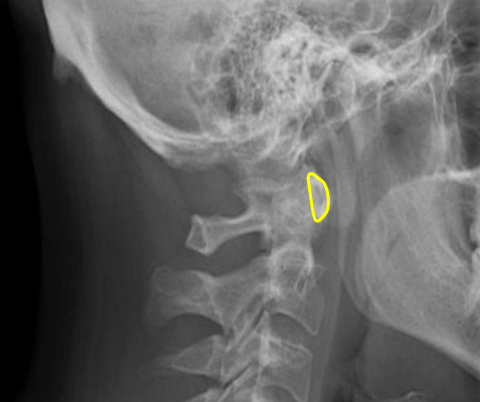

Odontoid process

Atlanto-Dental interspace